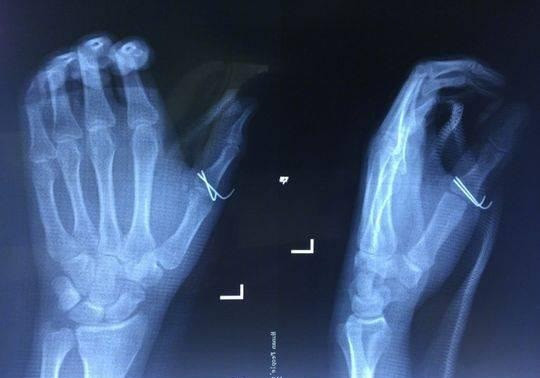

Ngay sau đó, anh Hòa đến bệnh viện để cấp cứu và được các bác sĩ cho biết, vết thương của anh tương đối nặng, rách, thủng khoảng 7cm ở miệng bàn tay trái, buộc phải khâu lại và băng bó điều trị.